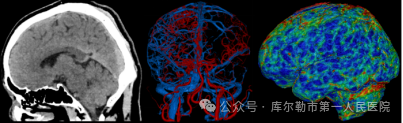

2、一站式卒中检查-立体直观全脑覆盖

超高端320排CT可实现单圈扫描的全脑覆盖成像,一次检查即可获得全脑平扫图像、动静脉造影图像和灌注图像,以及缺血半暗带和核心梗死区的分析,不仅可应用于急诊缺血性脑卒中的影像评估,还可助力脑血管畸形、脑动脉瘤等其他脑血管病的结构和功能评估,同时配以低剂量平台,保证患者在低剂量水平完成卒中扫描。